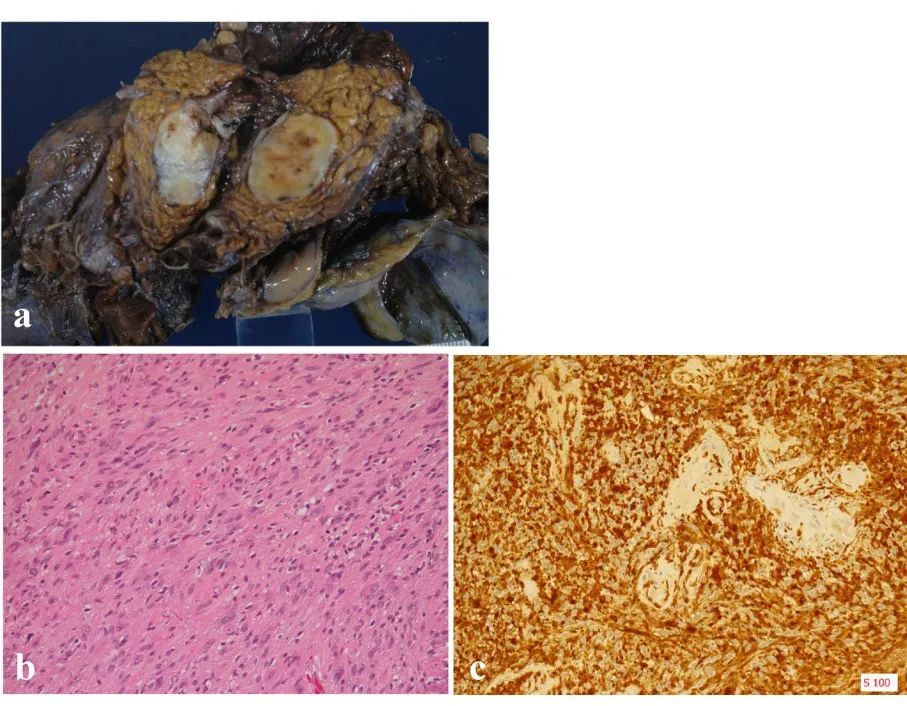

行保胃胰十二指肠切除术(SSSPD)以明确诊断。切除的标本显示在胰头有一个包裹良好的边界肿块,约 2.0 厘米。组织病理学检查显示肿瘤内梭形细胞增生,呈交错和栅栏状。增殖细胞无异型性,有丝分裂较少。免疫组化结果显示,梭形细胞中 S-100 蛋白呈阳性

图 2.4 从宏观上看,肿瘤是一个包裹良好的边界肿块 (a). 组织病理学检查显示梭形细胞增生,肿瘤内呈交错和栅栏状。增殖细胞无异型性,有丝分裂较少(苏木精-伊红染色 ×200)(b). 免疫组化结果显示,梭形细胞中 S-100 蛋白 (c). 呈阳性